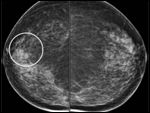

Digital mammography shows area of calcifications (Figure 1a-b). Magnification views demonstrate intraductal pleomorphic microcalcifications in the right 11:00 area (Figure 1c).

Vacuum assisted stereotactic needle core biopsy of the right breast 11:00 microcalcifications reveals ductal carcinoma in situ.